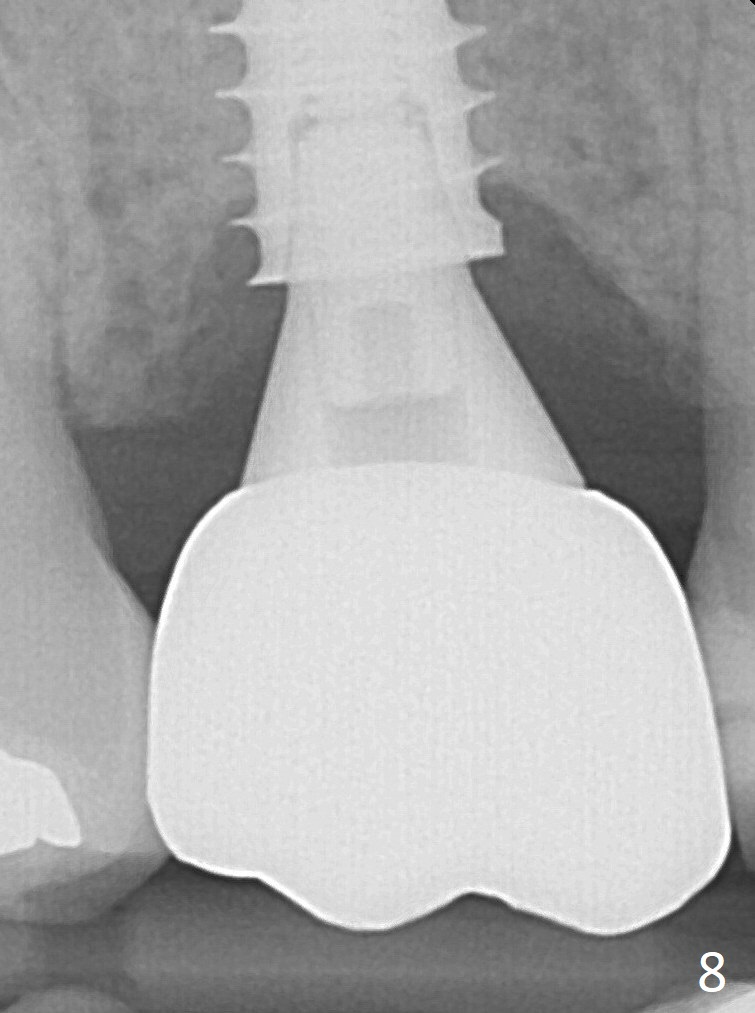

The implant was placed deep enough without thread exposure; now with apparently complete abutment seating (Fig.11). The similar complication may recur due to refusal to have implant at #19 (fear of nerve injury).